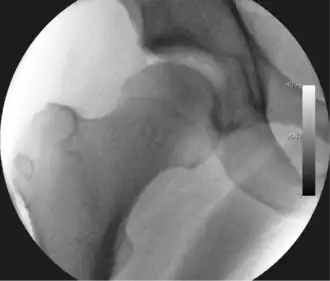

Figure 3. Fluoroscopic picture showing a mild amount of distraction of the hip before insertion of any instruments -

The procedure is performed with the patient asleep (general anaesthetic) or under spinal anaesthesia. There are two widely used methods, one with the patient on their back (supine) and the other on their side (lateral decubitus). Which is used is down to the surgeon's preference. To gain access to the central compartment of the hip joint (between the ball and socket), traction is applied to the affected leg after placing the foot into a special boot. (See fig. 2) There is specifically designed equipment for this, although some surgeons use a 'traction table', initially designed to help in the operative fixation of broken thigh and lower leg bones. The amount of traction (or pull) needed is assessed with the help of fluoroscopy (low-dose portable x-ray). (See fig. 3) It is usually not possible to distract the ball from the socket with traction alone by more than a few millimetres. Once the surgeon is happy that they will be able to gain access to the hip joint (i.e. the ball will distract from the socket by a small amount), the patient is then painted with antiseptic and the surgical drapes applied.

The next step is to insert a fine needle under x-ray guidance into the hip joint. This breaks the 'suction seal' of the joint and allows further distraction if necessary (see fig 4). The surgeon wishes to see the ball move out the socket by approximately 1 cm, so that access to the hip joint can be achieved with minimal risk of damage to the joint surfaces. Most surgeons will inject fluid into the joint at this stage, again to ensure that there is enough space between the ball and socket for safe instrument access. This needle is then removed. The next step is placement of the 'portals', or the small holes made to pass instruments into the joint. This is achieved by again passing a fresh hollow needle into the joint under x-ray control, usually in a slightly different position. The reason for this is so the surgeon can ensure that the needle, and subsequent cannulae do not penetrate and damage the acetabular labrum or cartilage joint surfaces (see fig. 5). Again, surgeons will have their own preferences as to their preferred placement. Through this hollow needle, a long thin flexible guide wire is passed into the joint, and the needle is removed over it, leaving the guide wire in situ. A small cut in the skin is made around the wire, to allow for larger cannulae to be placed over the wire through the portal. The wire therefore guides the larger cannulae into the joint. The most common external diameters of cannulae used are between 4.5 and 5.5 mm. Once the surgeon is satisfied that the cannula is in the correct position, by a combination of feel and x-ray guidance, the guide wire can be withdrawn. Once the first portal is correctly placed, any further portals may be created once the camera is in position, to ensure that they are placed with minimal risk to the joint surfaces. This process can be repeated to gain as many points of entry to the hip joint as the surgeon requires, normally between two and four. Certain of these entry points will be used for the viewing arthroscope and others for operating instruments.